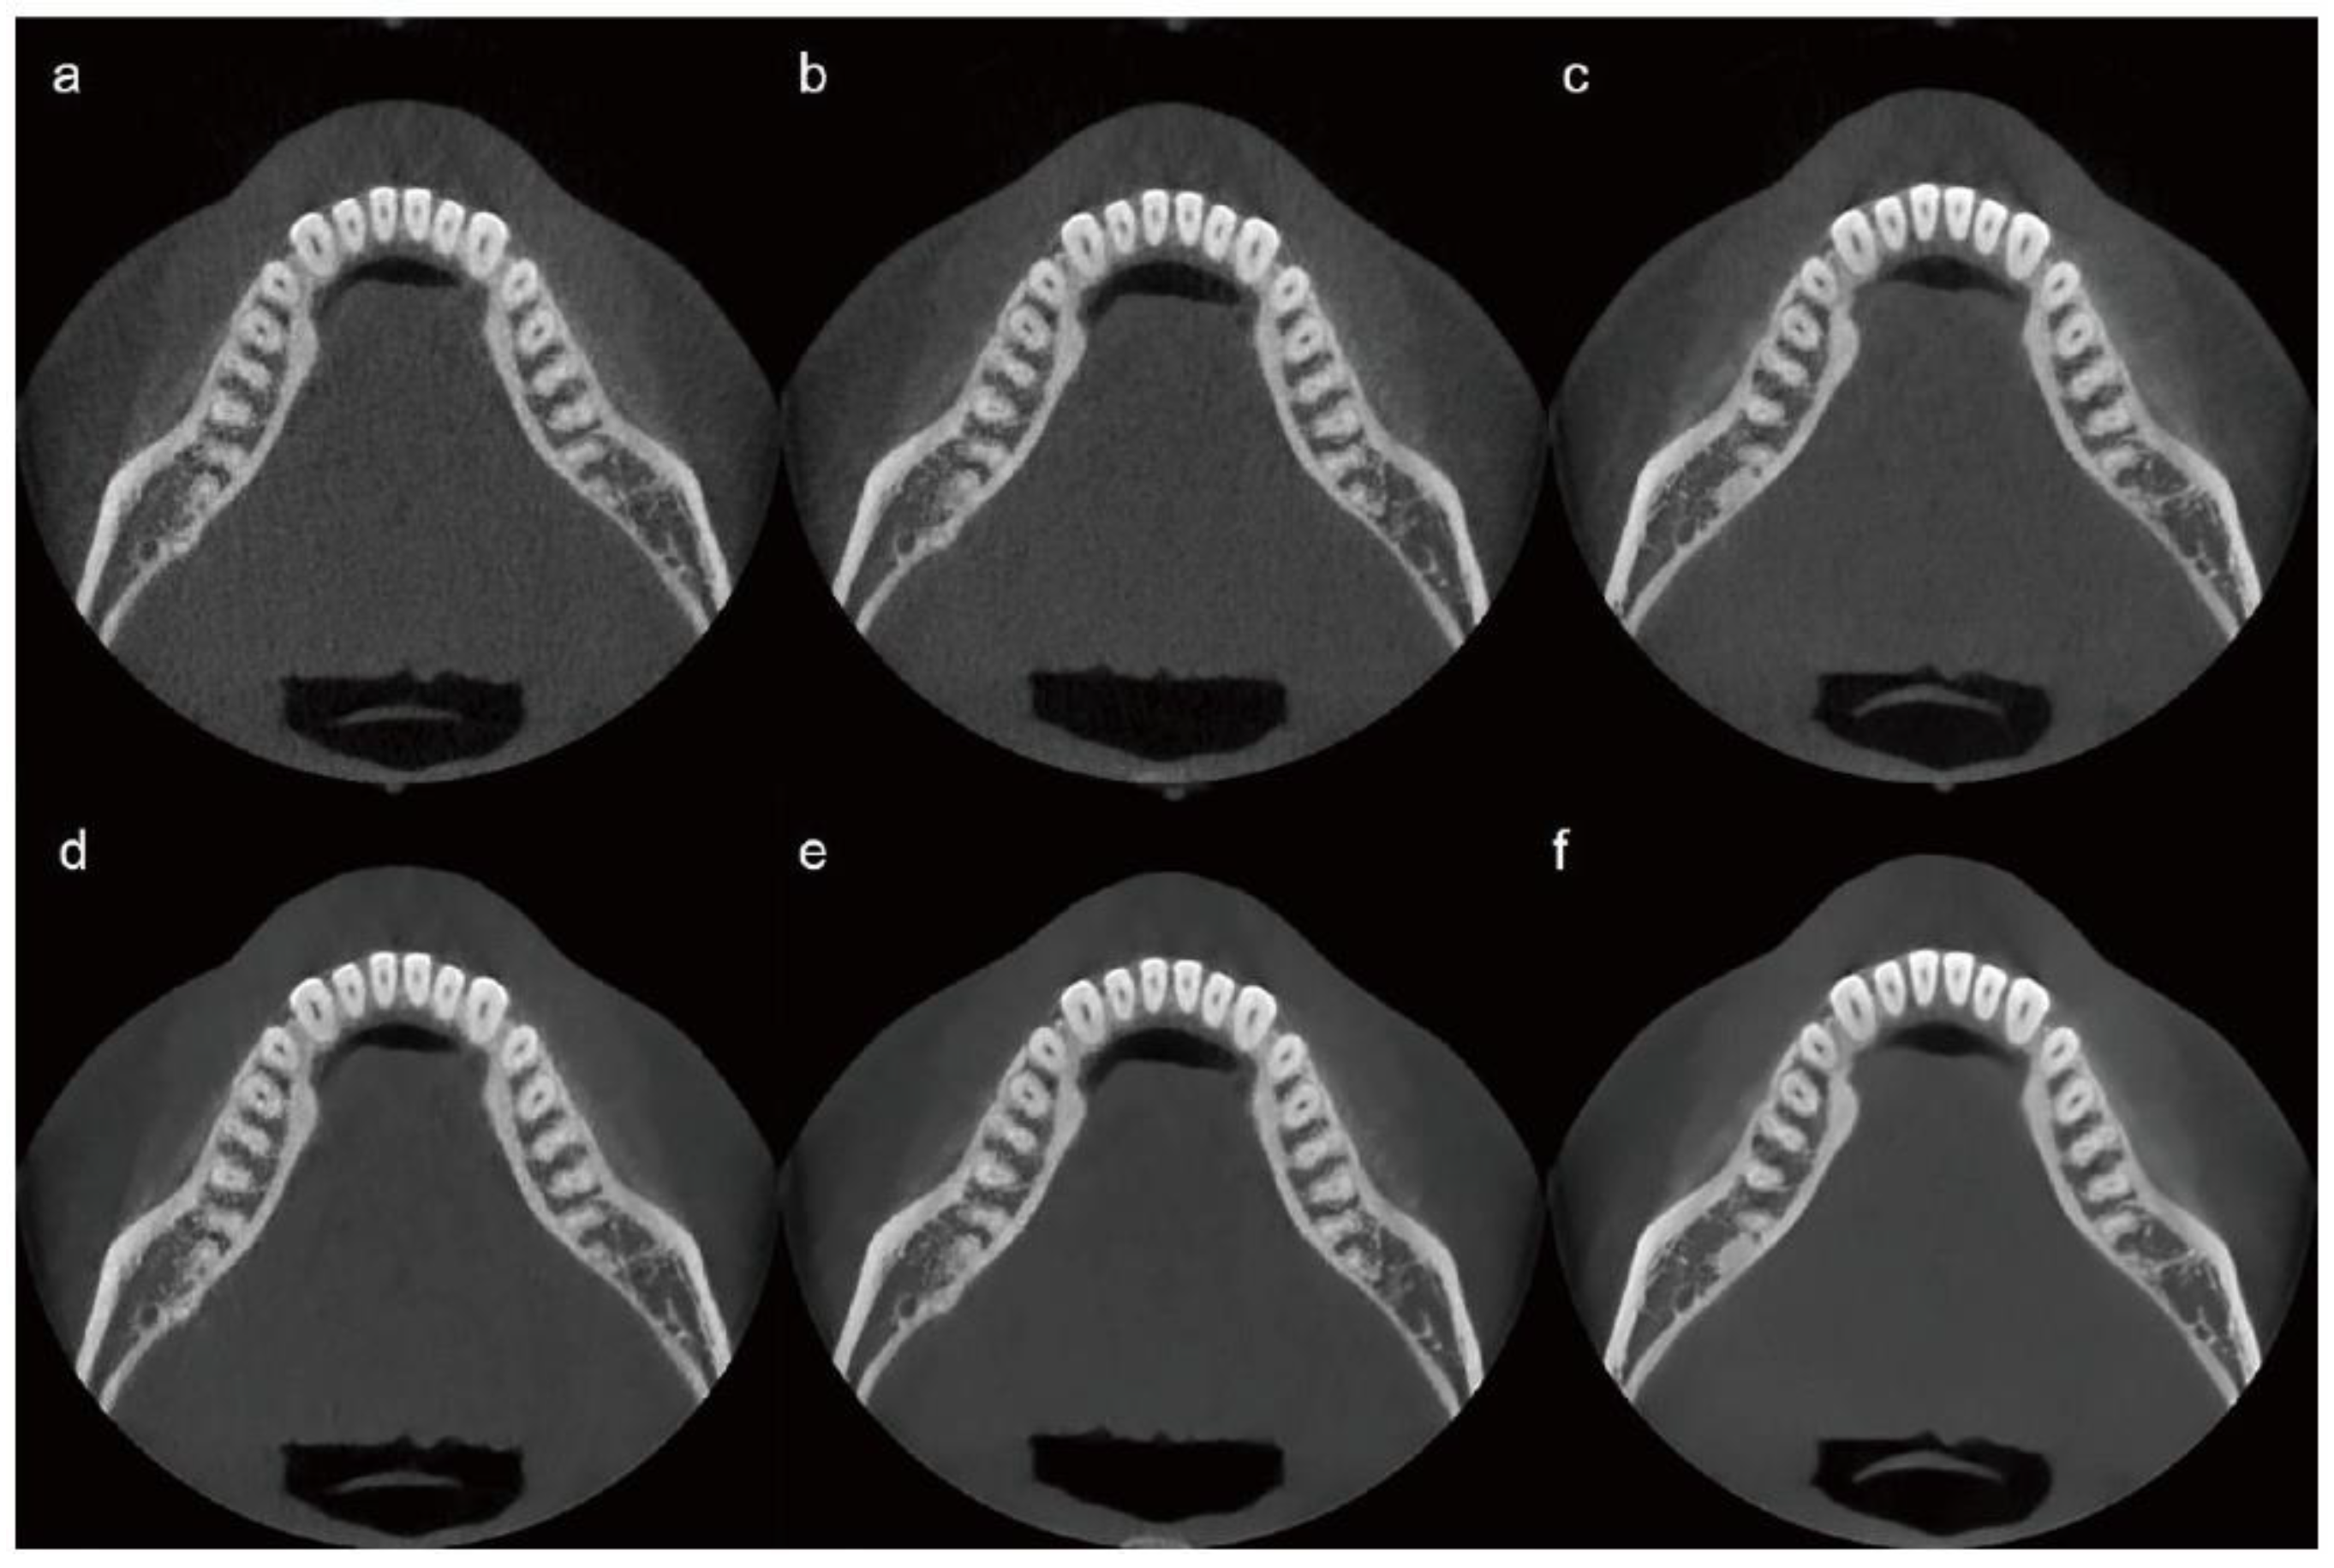

A single-subject, intra-individual study design was employed to enable direct comparison of CBCT images acquired under different radiation dose conditions while minimizing anatomical variability. The use of a single healthy adult male without maxillofacial pathology provided a consistent anatomical reference, allowing controlled assessment of technical image quality changes associated with dose reduction and AI-based post-processing. This approach was selected for this exploratory feasibility study to support consistent visual comparisons across dose levels while adhering to the ALARA (As Low As Reasonably Achievable) principle by limiting unnecessary radiation exposure. The limitations inherent to a single-subject design are acknowledged and are addressed in the Discussion. Scans were performed at three radiation dose levels: 10%, 20%, and 100% of the standard clinical dose. These initial scans, referred to as “raw images,” were not subjected to AI processing. Each raw image was subsequently processed using an AI-based image enhancement algorithm, resulting in three additional image sets termed “AI-processed images.” Six image sets were thus prepared and categorized according to the radiation dose level and AI processing status as follows: Image 1 (10% dose, raw image), Image 2 (10% dose, AI-processed), Image 3 (20% dose, raw image), Image 4 (20% dose, AI-processed), Image 5 (100% dose, raw image), and Image 6 (100% dose, AI-processed). CBCT was performed using a Bright CT scanner (Dentium; Suwon, Republic of Korea).

For the 10% dose image set, the parameters were 85 kVp, 8.5 mA, and 16 ms, resulting in a DAP of 193.38 µGy·m2. For the 20% dose image set, the parameters were adjusted to 85 kVp, 9 mA, and 16 ms, yielding a DAP of 386.77 µGy·m2. The detailed CBCT scanning protocols, including kVp, mA, ms, and DAP, are summarized in Table 1. Representative images from each protocol are shown in Figure 2.

Figure 2.

CBCT image sets categorized by radiation dose level and AI processing status. (a) 10% dose, raw image; (b) 20% dose, raw image; (c) 100% dose, raw image; (d) 10% dose, AI-processed image; (e) 20% dose, AI-processed image; (f) 100% dose, AI-processed image. AI, artificial intelligence; CBCT, cone-beam computed tomography.